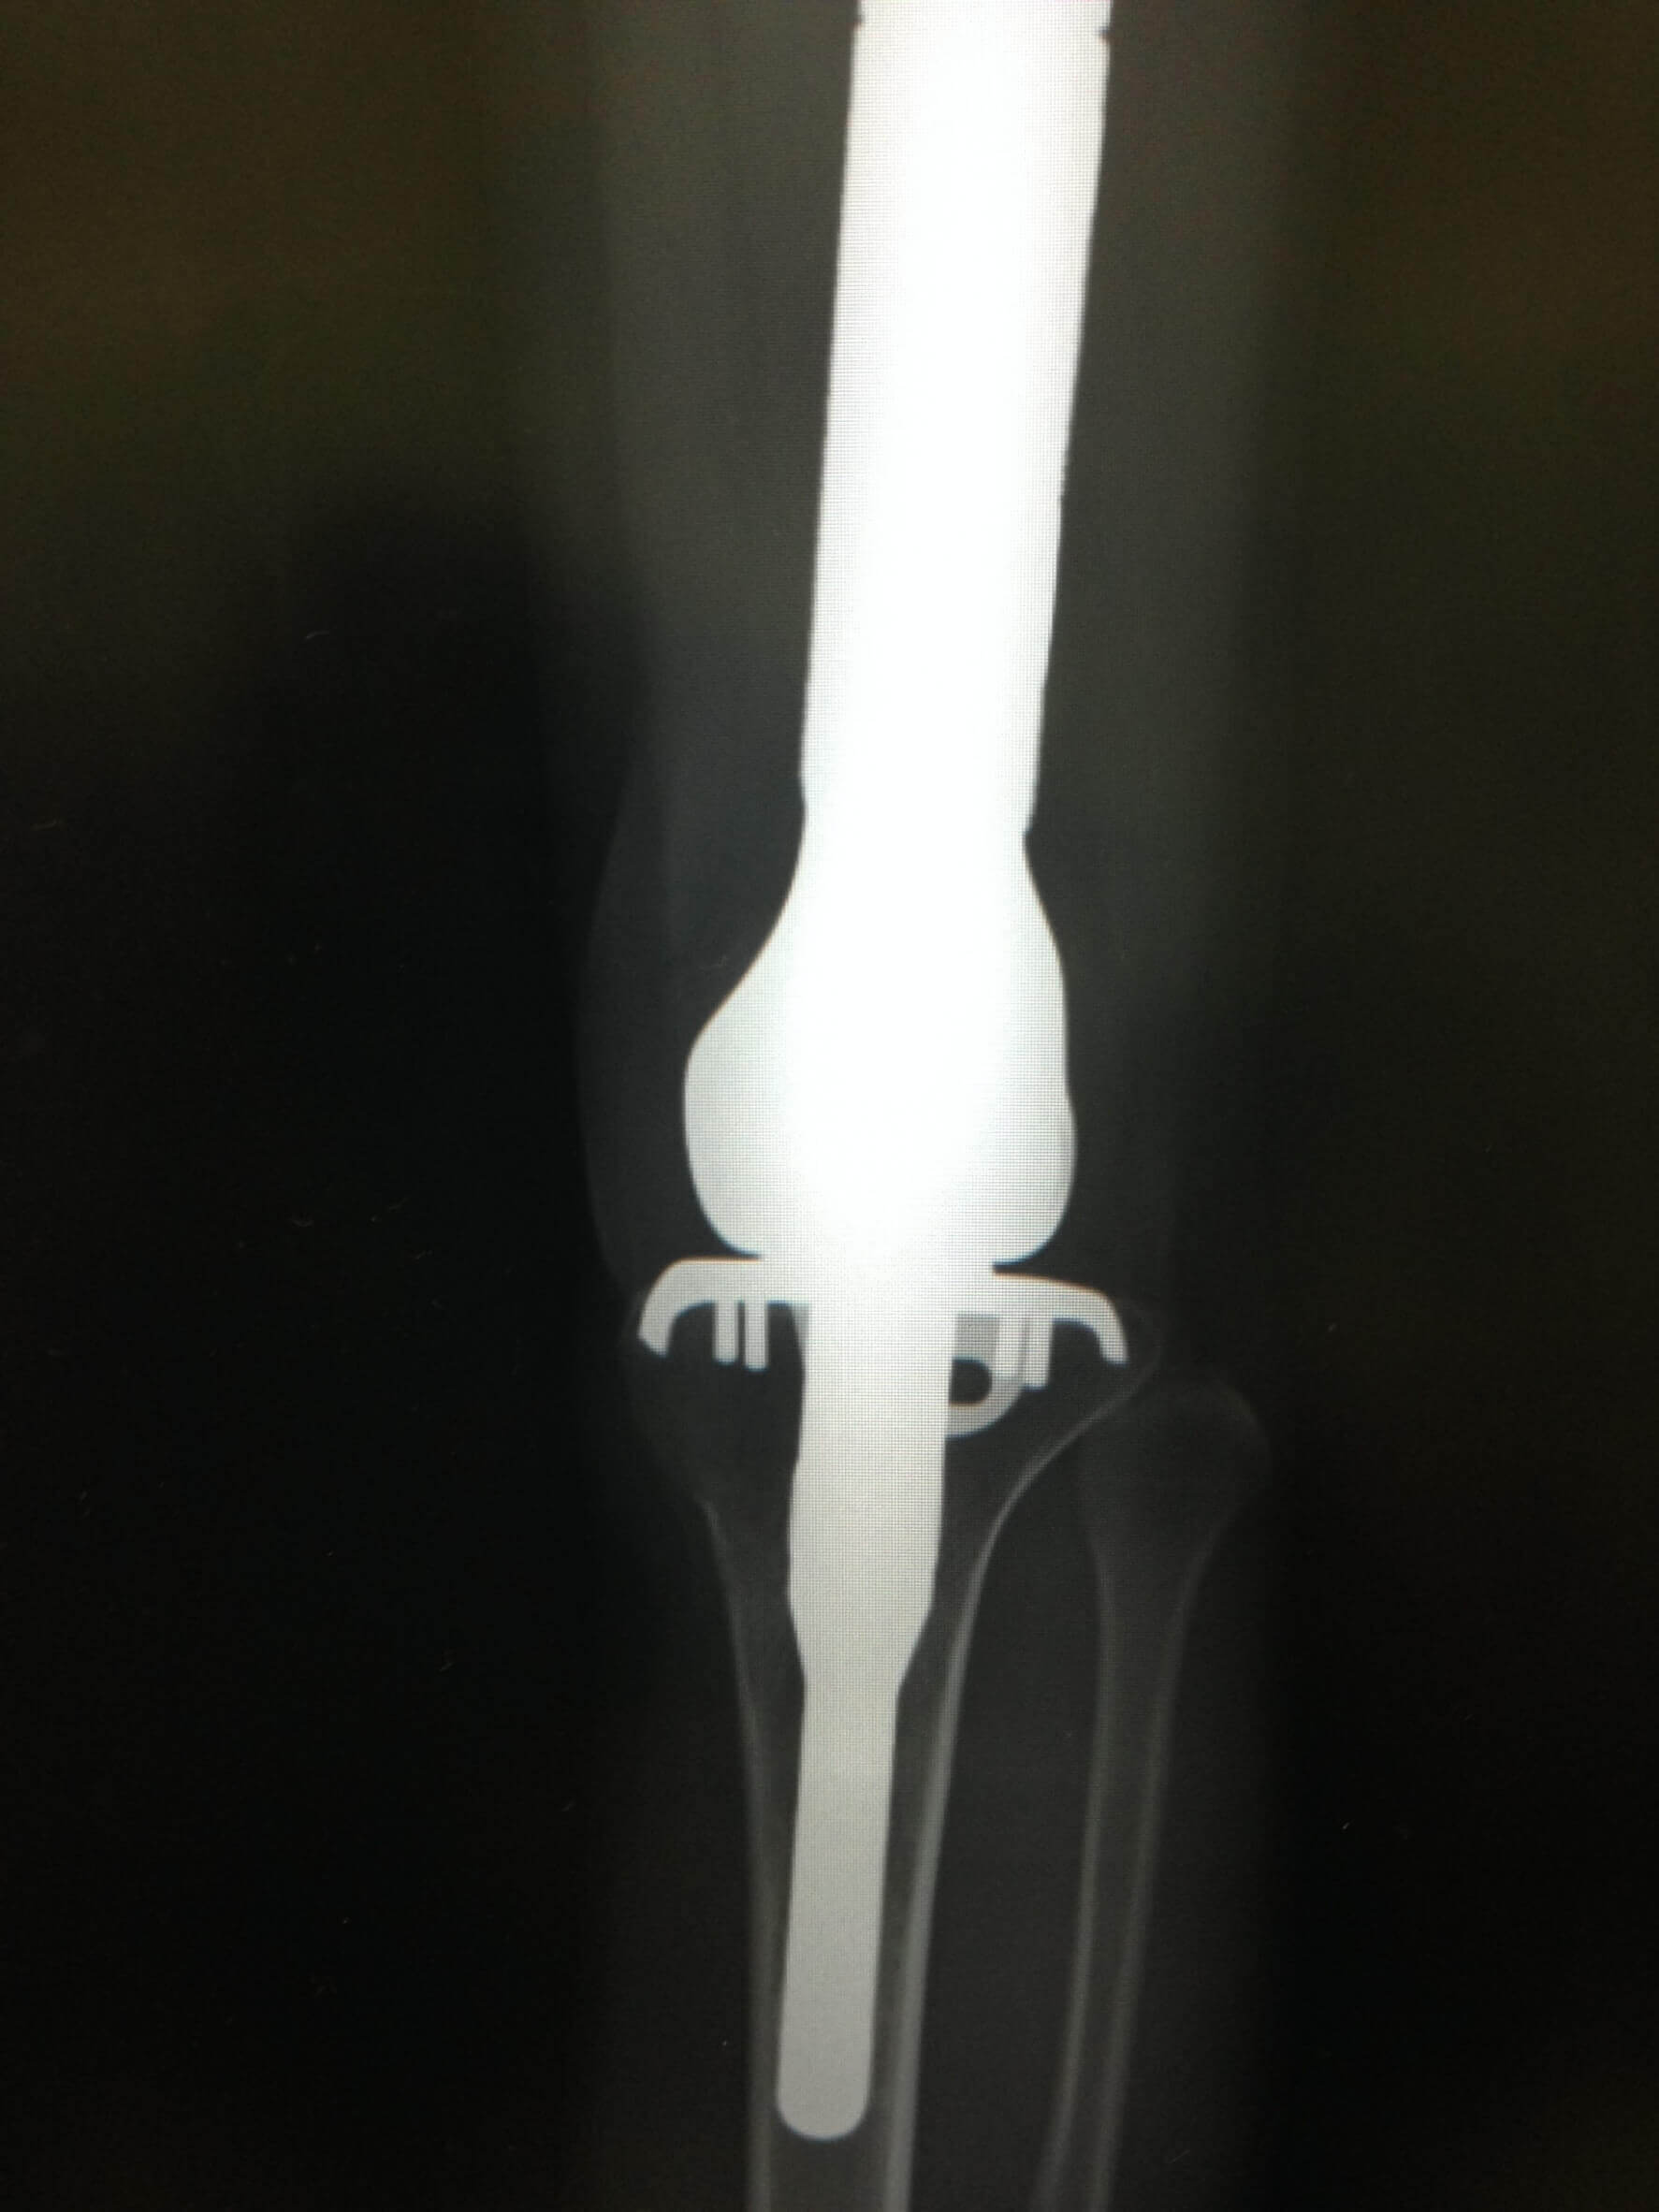

“骨肉腫”、骨にできるガンです。

ガン細胞に侵された左膝の骨を取り除き、

人工関節を入れる手術を受けました。

KSK, who was a baseball kid, became ill when he was fifteen. It was an "osteosarcoma",which is a cancerous tumor in a bone.

He went through an operation in which they removed the part of his cancerous left knee bone,and replaced it with an artificial joint.

当KSK还是个棒球少年时,15岁就被诊断出患有疾病。"骨肉瘤",也就是骨癌。

他接受了手术,切除了左膝受癌细胞影响的骨头,并植入了人工关节。